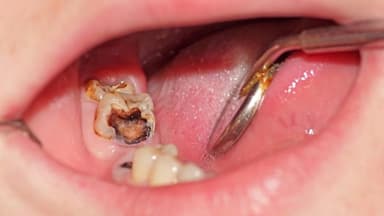

Khi sâu răng hàm trẻ em tiến triển nghiêm trọng hơn, các triệu chứng thường trở nên rõ rệt, bao gồm cảm giác đau khi nhai hoặc khi tiếp xúc với thức ăn nóng, lạnh, ngọt; xuất hiện hố sâu dễ nhận thấy trên bề mặt răng hàm; nướu quanh răng bị sâu sưng đỏ; và hơi thở có mùi hôi đặc trưng phát ra từ khu vực răng tổn thương.

3.3. Giai đoạn biến chứng sâu răng hàm ở trẻ

Nếu không được điều trị kịp thời, sâu răng hàm trẻ em có thể gây ra những biến chứng như áp xe răng do nhiễm trùng lan rộng khiến má sưng to, sốt do tình trạng nhiễm trùng nghiêm trọng, khó nhai khiến trẻ tránh sử dụng răng bị đau, và nguy hiểm hơn là ảnh hưởng đến mầm răng vĩnh viễn bên dưới.